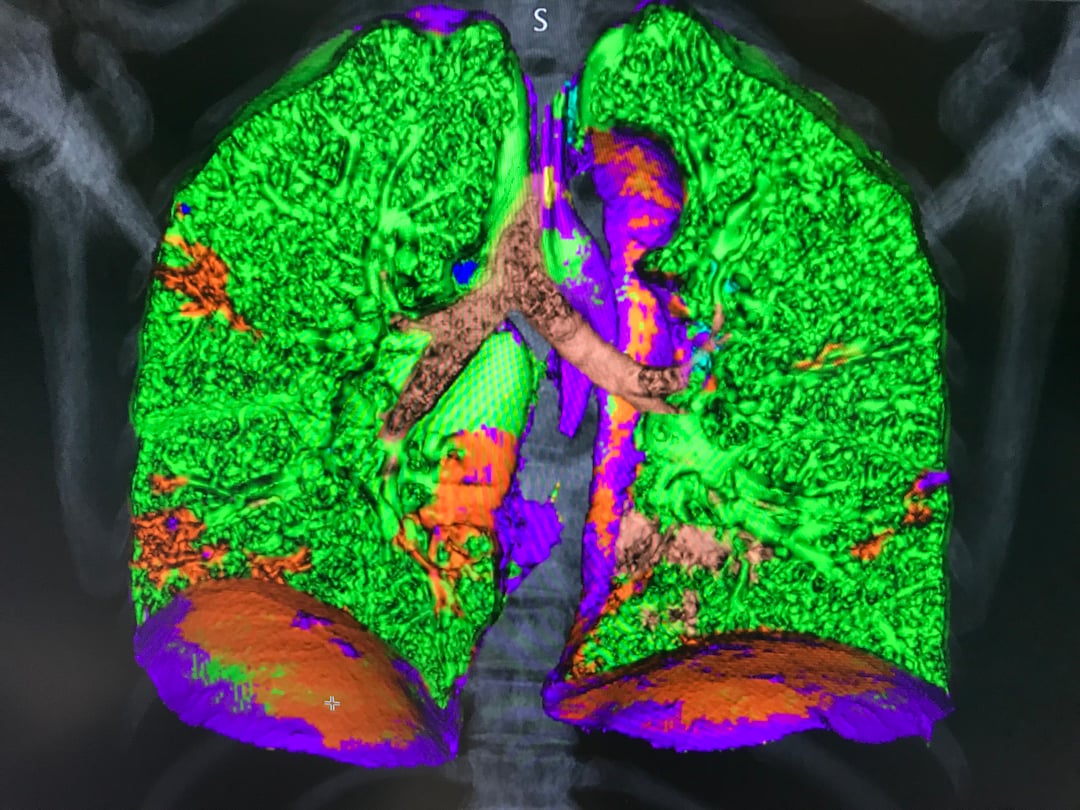

This photo gallery shows the variety of radiological presentations of COVID-19 (SARS-CoV-2) in medical imaging, including computed tomography (CT), radiograph X-rays, ultrasound, echocardiograms and magnetic resonance imaging (MRI). The radiology images show examples of typical COVID pneumonia in the lungs and the numerous complications the virus causes in the body in multiple organs, including the brain, kidneys, heart, abdomen and vascular system.

Ultrasound, especially hand-held ultrasound imaging devices, have become a primary imaging modality for novel coronavirus because of the ease to bag the device and sterilize it after use. CT and mobile X-ray systems are also used as front-line imaging systems for COVID-positive or suspected COVID patients.